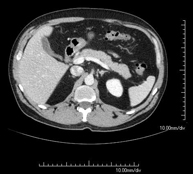

Prova diagnòstica que consisteix en l'estudi de l'abdomen d'alta definició anatòmica (fetge, vesícula biliar, via biliar, pàncrees, melsa, estómac, intestins, ronyons, estructures vasculars, bufeta, úter i ovaris, etc.) mitjançant l'ús d'un equip de TC (Tomografia Computeritzada). Aquestes imatges s'estudien posteriorment en una estació de treball que permet obtenir reconstruccions bidimensionals en diferents plànols de l'espai i també reconstruccions 3D (volumètriques). La majoria d'estudis requereixen l'ús de contrast iodat per millorar la definició de les imatges. - TC Pelvis

Prova diagnòstica que consisteix en obtenir imatges bi i tridimensionals de l'abdomen d'alta definició anatòmica (estructures òssies, estructures vasculars, fetge, pàncrees, vesícula biliar, ronyons, glàndules suprarenals, melsa, intestí prim i gros, bufeta, úter i ovaris, pròstata i vesícules seminals, urèters, etc.) mitjançant l'ús d'un equip de TC (Tomografia Computeritzada). La majoria d'estudis requereixen l'ús de contrast iodat. - TC Fetge